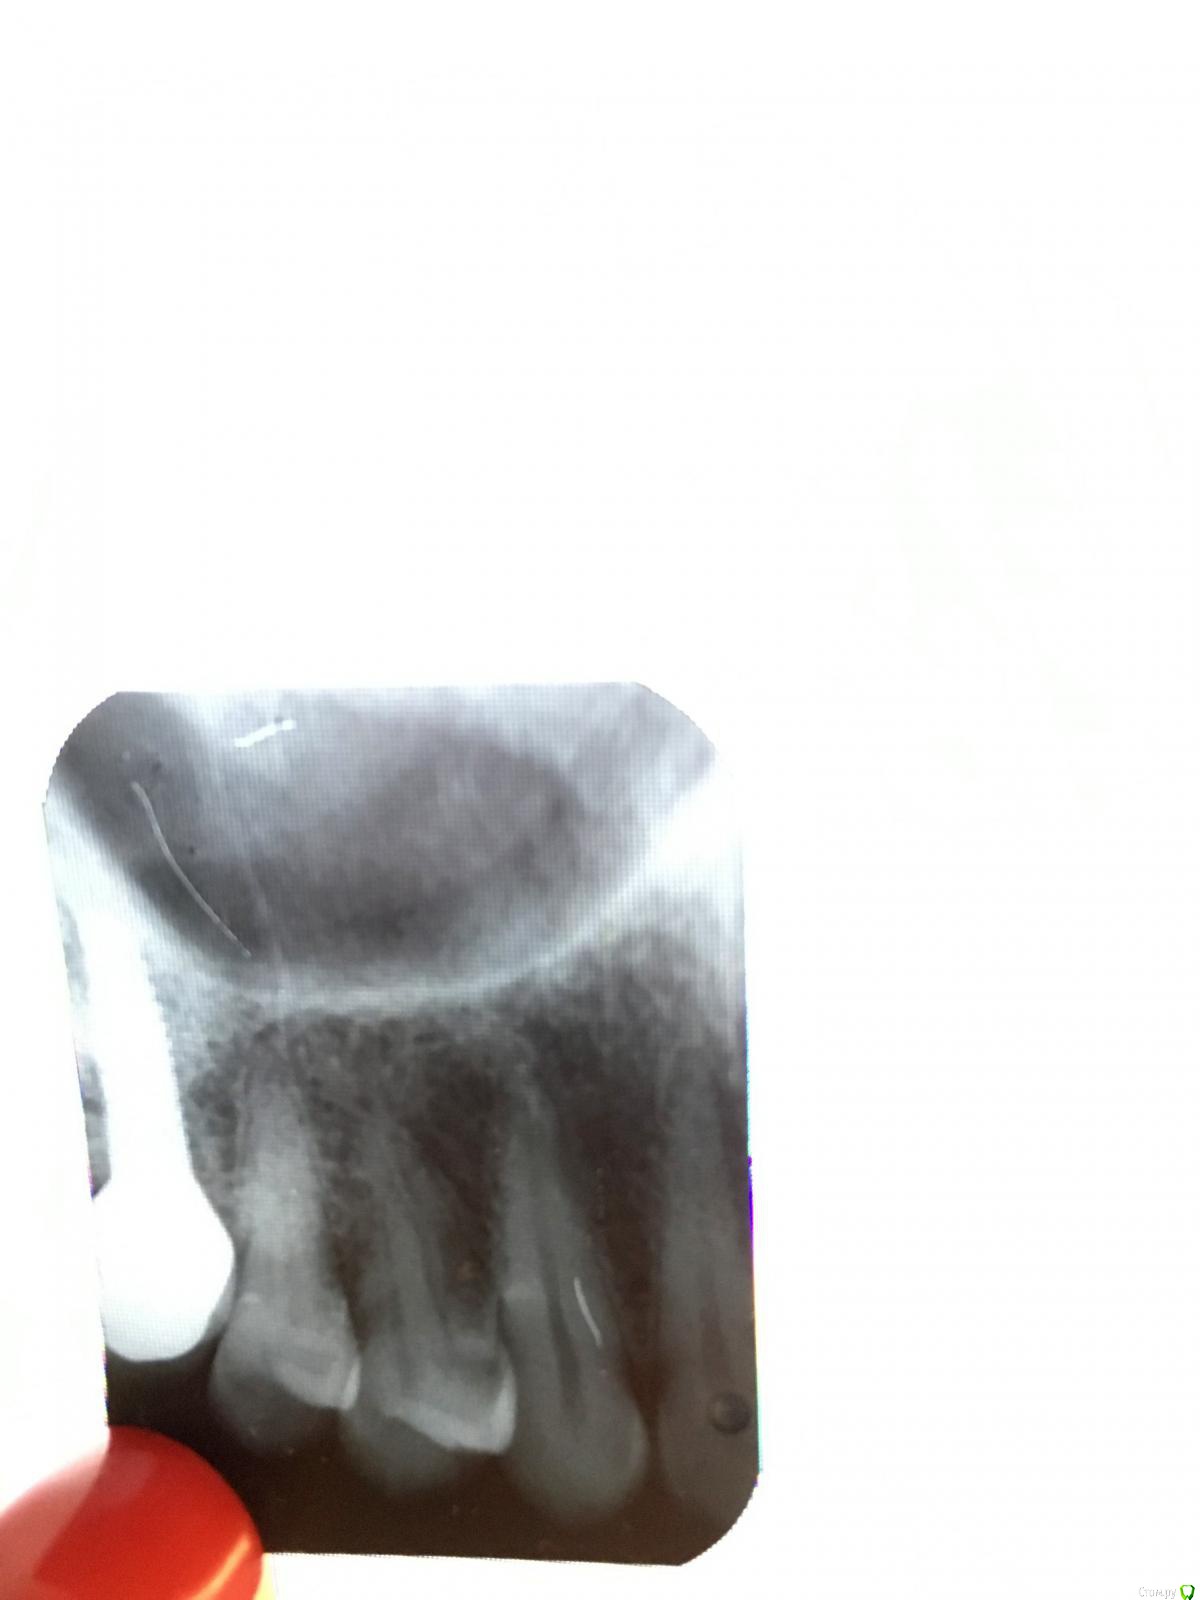

Ольгаxxx Опубликовано 12 ноября, 2019 Поделиться Опубликовано 12 ноября, 2019 (изменено) Здравствуйте, уважаемые врачи данного форума. Надеюсь, Вы мне поможете своим профессиональным советом. Итак, была на консультации у бюджетного стоматолога, так как дорогую клинику, где лечила зубы не тяну.Обратилась, так как происходила реакция зуба на сладкое (не понятно какого, то ли 5, то ли 4 сверху), врач явного прям кариеса не увидел, но заметил шероховатую пигментацию между коронкой и 5кой, внизу зуба, говорит, что нужен прицельный снимок, снимок сделала, прилагаю. Так же врач говорил, что оттого что объем кости немного ушел (была имплантация 6 и 7), шейка зуба может так реагировать.Очень хочется знать, стоит ли что-то делать с зубом и есть ли кариес на снимке? И если делать, то врач предлагает не сверху сверлить, а между зубами снизу и потом закрыть японским каким-то герметиком, так вроде поняла. Нормальный он метод предлагает не сверху, а снизу? Сможет ли он убрать так кариес, если он там есть?Ув. врачи, спасибо, если откликнетесь.И второй снимок сделан летом, может что изменилось, посмотрите , плиз. Изменено 12 ноября, 2019 пользователем Ольгаxxx Ссылка на комментарий

shishok Опубликовано 12 ноября, 2019 Поделиться Опубликовано 12 ноября, 2019 Кариозная полость на 4 зубе(на контакте с 3). Лечить. 1 Ссылка на комментарий

Ольгаxxx Опубликовано 12 ноября, 2019 Автор Поделиться Опубликовано 12 ноября, 2019 (изменено) Кариозная полость на 4 зубе(на контакте с 3). Лечить.Огромное спасибо, за скорый ответ. Кариес глубокий уже, раз реакция на сладкое? Не могу понять, как врач мог осматривать зуб и не увидеть этого, тем более есть жалоба на реакцию сладкого. Но правда снимки я ему еще не показывала. На 6ке снизу , есть темное пятно, врач с дорогой клиники советовал наблюдать, сегодняшний врач сказал сделать снимок именно коронковой части. Снимок сделала, можно ли утверждать, что там кариес? Можно ли у Вас узнать?( Изменено 12 ноября, 2019 пользователем Ольгаxxx Ссылка на комментарий

red_butler Опубликовано 12 ноября, 2019 Поделиться Опубликовано 12 ноября, 2019 Снимки не информативны Ссылка на комментарий

Ольгаxxx Опубликовано 12 ноября, 2019 Автор Поделиться Опубликовано 12 ноября, 2019 Снимки не информативныИ с верхним снимком тоже? То есть под вопросом кариес? Или там точно есть? Ссылка на комментарий